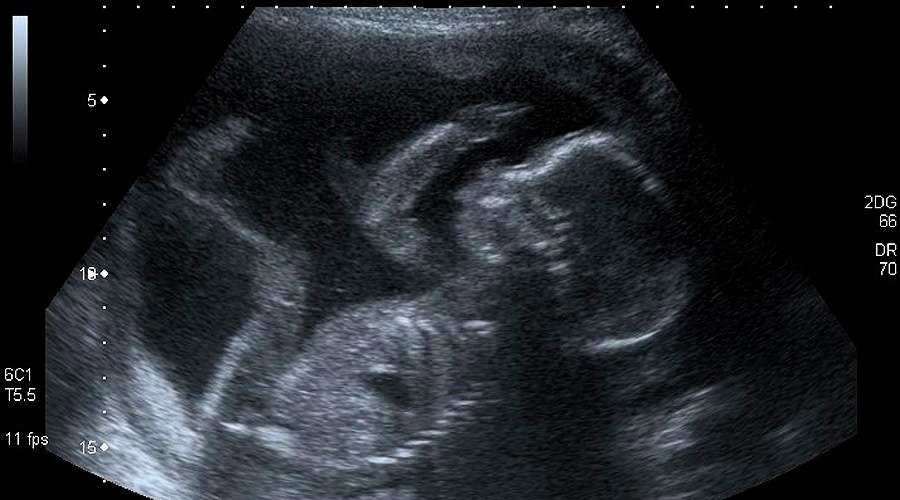

En esta época se ha difundido la postura abortista que no considera como ser humano al niño por nacer, pese a que es capaz de sentir dolor en el vientre materno, aunque la dignidad de la persona humana no depende de esto sino en su ser Hijo de Dios.

El National Catholic Register hizo una lista sobre lo que se sabe, a través de la ciencia, de todo aquello que experiementa el niño por nacer en el vientre materno.